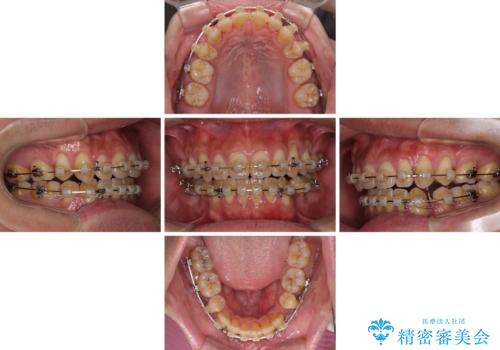

隙間が空いて突出した前歯を治したい ワイヤー装置による抜歯矯正

- クリアブラケット

- 上下前歯の隙間と口元の出っ張った感じを気にして来院された患者様です。

上下の隙間は舌突出癖によるもので、またその癖により前歯が前方に出ている状態でした。

口元の出っ張りを改善するため、上下左右第一小臼歯4本を抜去し、ワイヤー装置にて矯正治療を行うこととしました。

舌の突出癖を改善するためのトレーニングを指導していましたが、なかなか改善することができず、ワイヤー装置を外してからも上下前歯に隙間ができやすい状況でした。